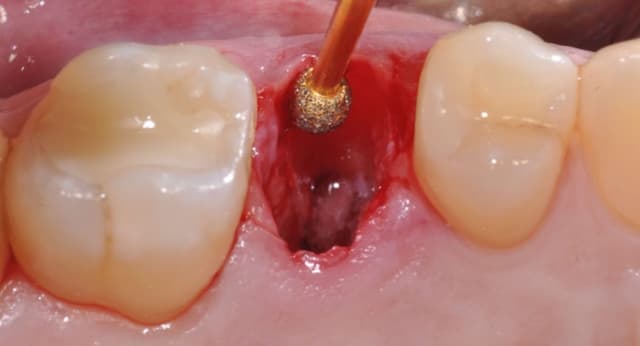

Nhổ răng khôn sau bao lâu thì hết chảy máu – Kinh nghiệm cần biết

Nhổ răng khôn là một phẫu thuật răng hàm mặt khá phổ biến trong nha khoa, tuy nhiên nhiều người bệnh vẫn lo lắng về tình trạng chảy máu sau phẫu thuật. Chảy máu sau khi nhổ răng khôn là hiện tượng bình thường, nhưng thời gian và mức độ chảy máu phụ thuộc vào […]